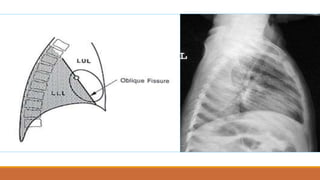

Các thùy phổi